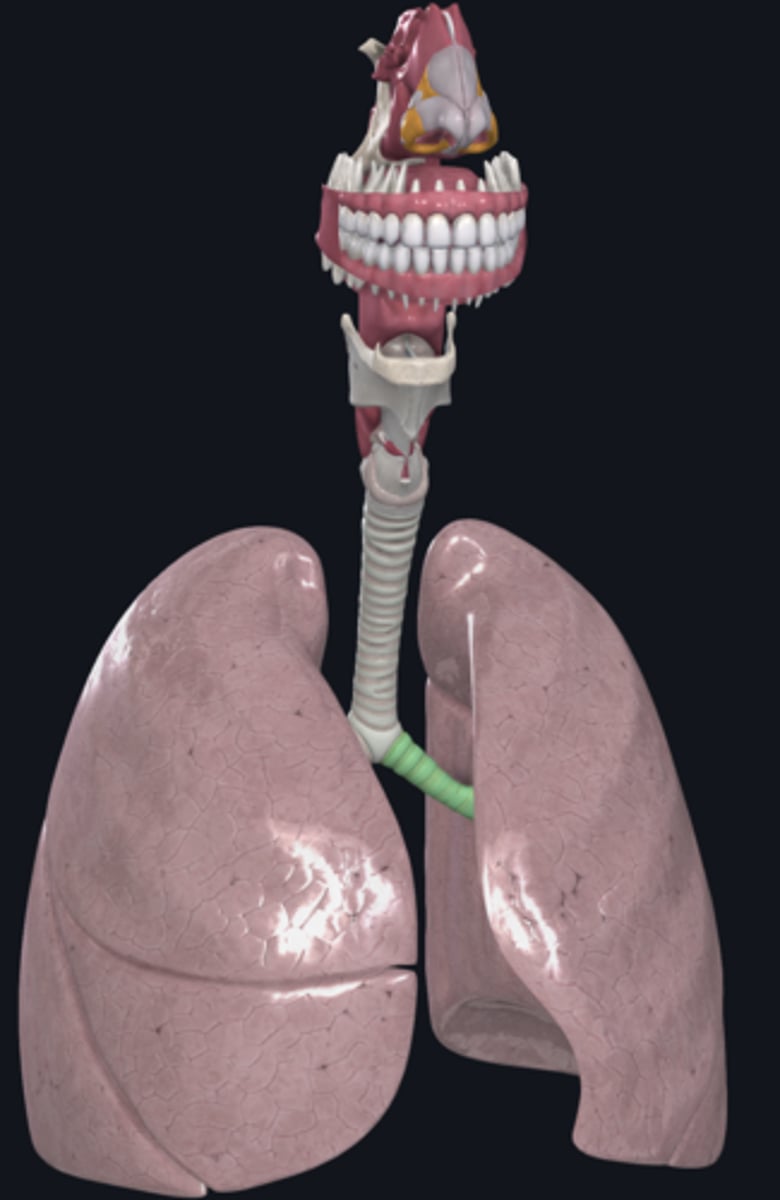

trachea

tracheal cartilage

right lung

left lung

nose

external nares

larynx

hyoid bone

thyroid cartilage

cricoid cartilage

trachea

tracheal cartilages

annular ligament

right main bronchus

left main bronchus